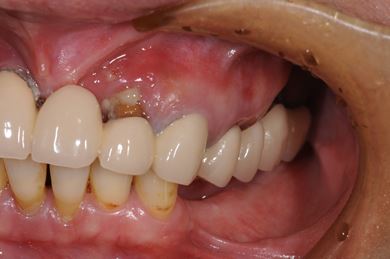

インプラントの症例写真 IMPLANT

インプラント治療+セラミック治療

| 主訴 | 上の奥歯がむし歯で治したい。下の歯が少ないので、インプラントか入れ歯、できれば併用で。 | ||||||||||||||||||||||||||||||||

| 治療方針 | インプラント治療にて、機能的・審美的回復を行う。 | ||||||||||||||||||||||||||||||||

| 治療内容 | インプラント3本、ハイブリッドセラミッククラウン5本 | ||||||||||||||||||||||||||||||||